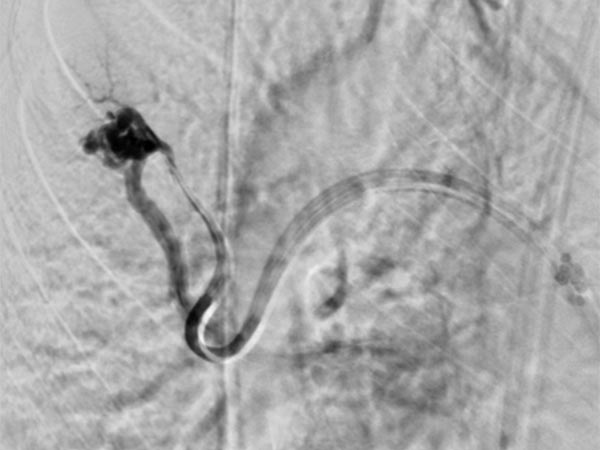

A guiding sheath was inserted into the right pulmonary artery from the neck (transjugular) via the heart, and a coaxial catheter was inserted through this by the Seldinger technique. After injection of contrast medium, pulmonary AVMs are also seen in the right lower lobe of the pulmonary circulation.

After cannulization of the larger pulmonary AVM, dilatation of the direct arteriovenous communication in the form of an aneurysm is seen. This is typical of Osler’s disease. The venous outflow is dilated, thus the risk of thromboembolism is particularly high.